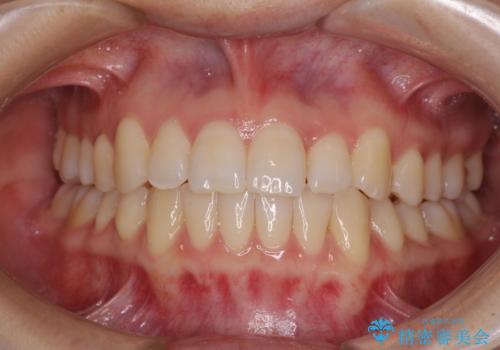

- 口元の突出感と口の閉じにくさ、前歯のデコボコを気にして来院された患者様です。

上下左右第一小臼歯4本を抜歯し、ワイヤー装置にて口元を引っ込めるよう矯正治療を行うこととしました。

骨格的に下顎骨が前方位にあるため、口元の突出感改善には限界があると思われましたが、唇の閉じにくさが改善するほど引っ込めることができました。